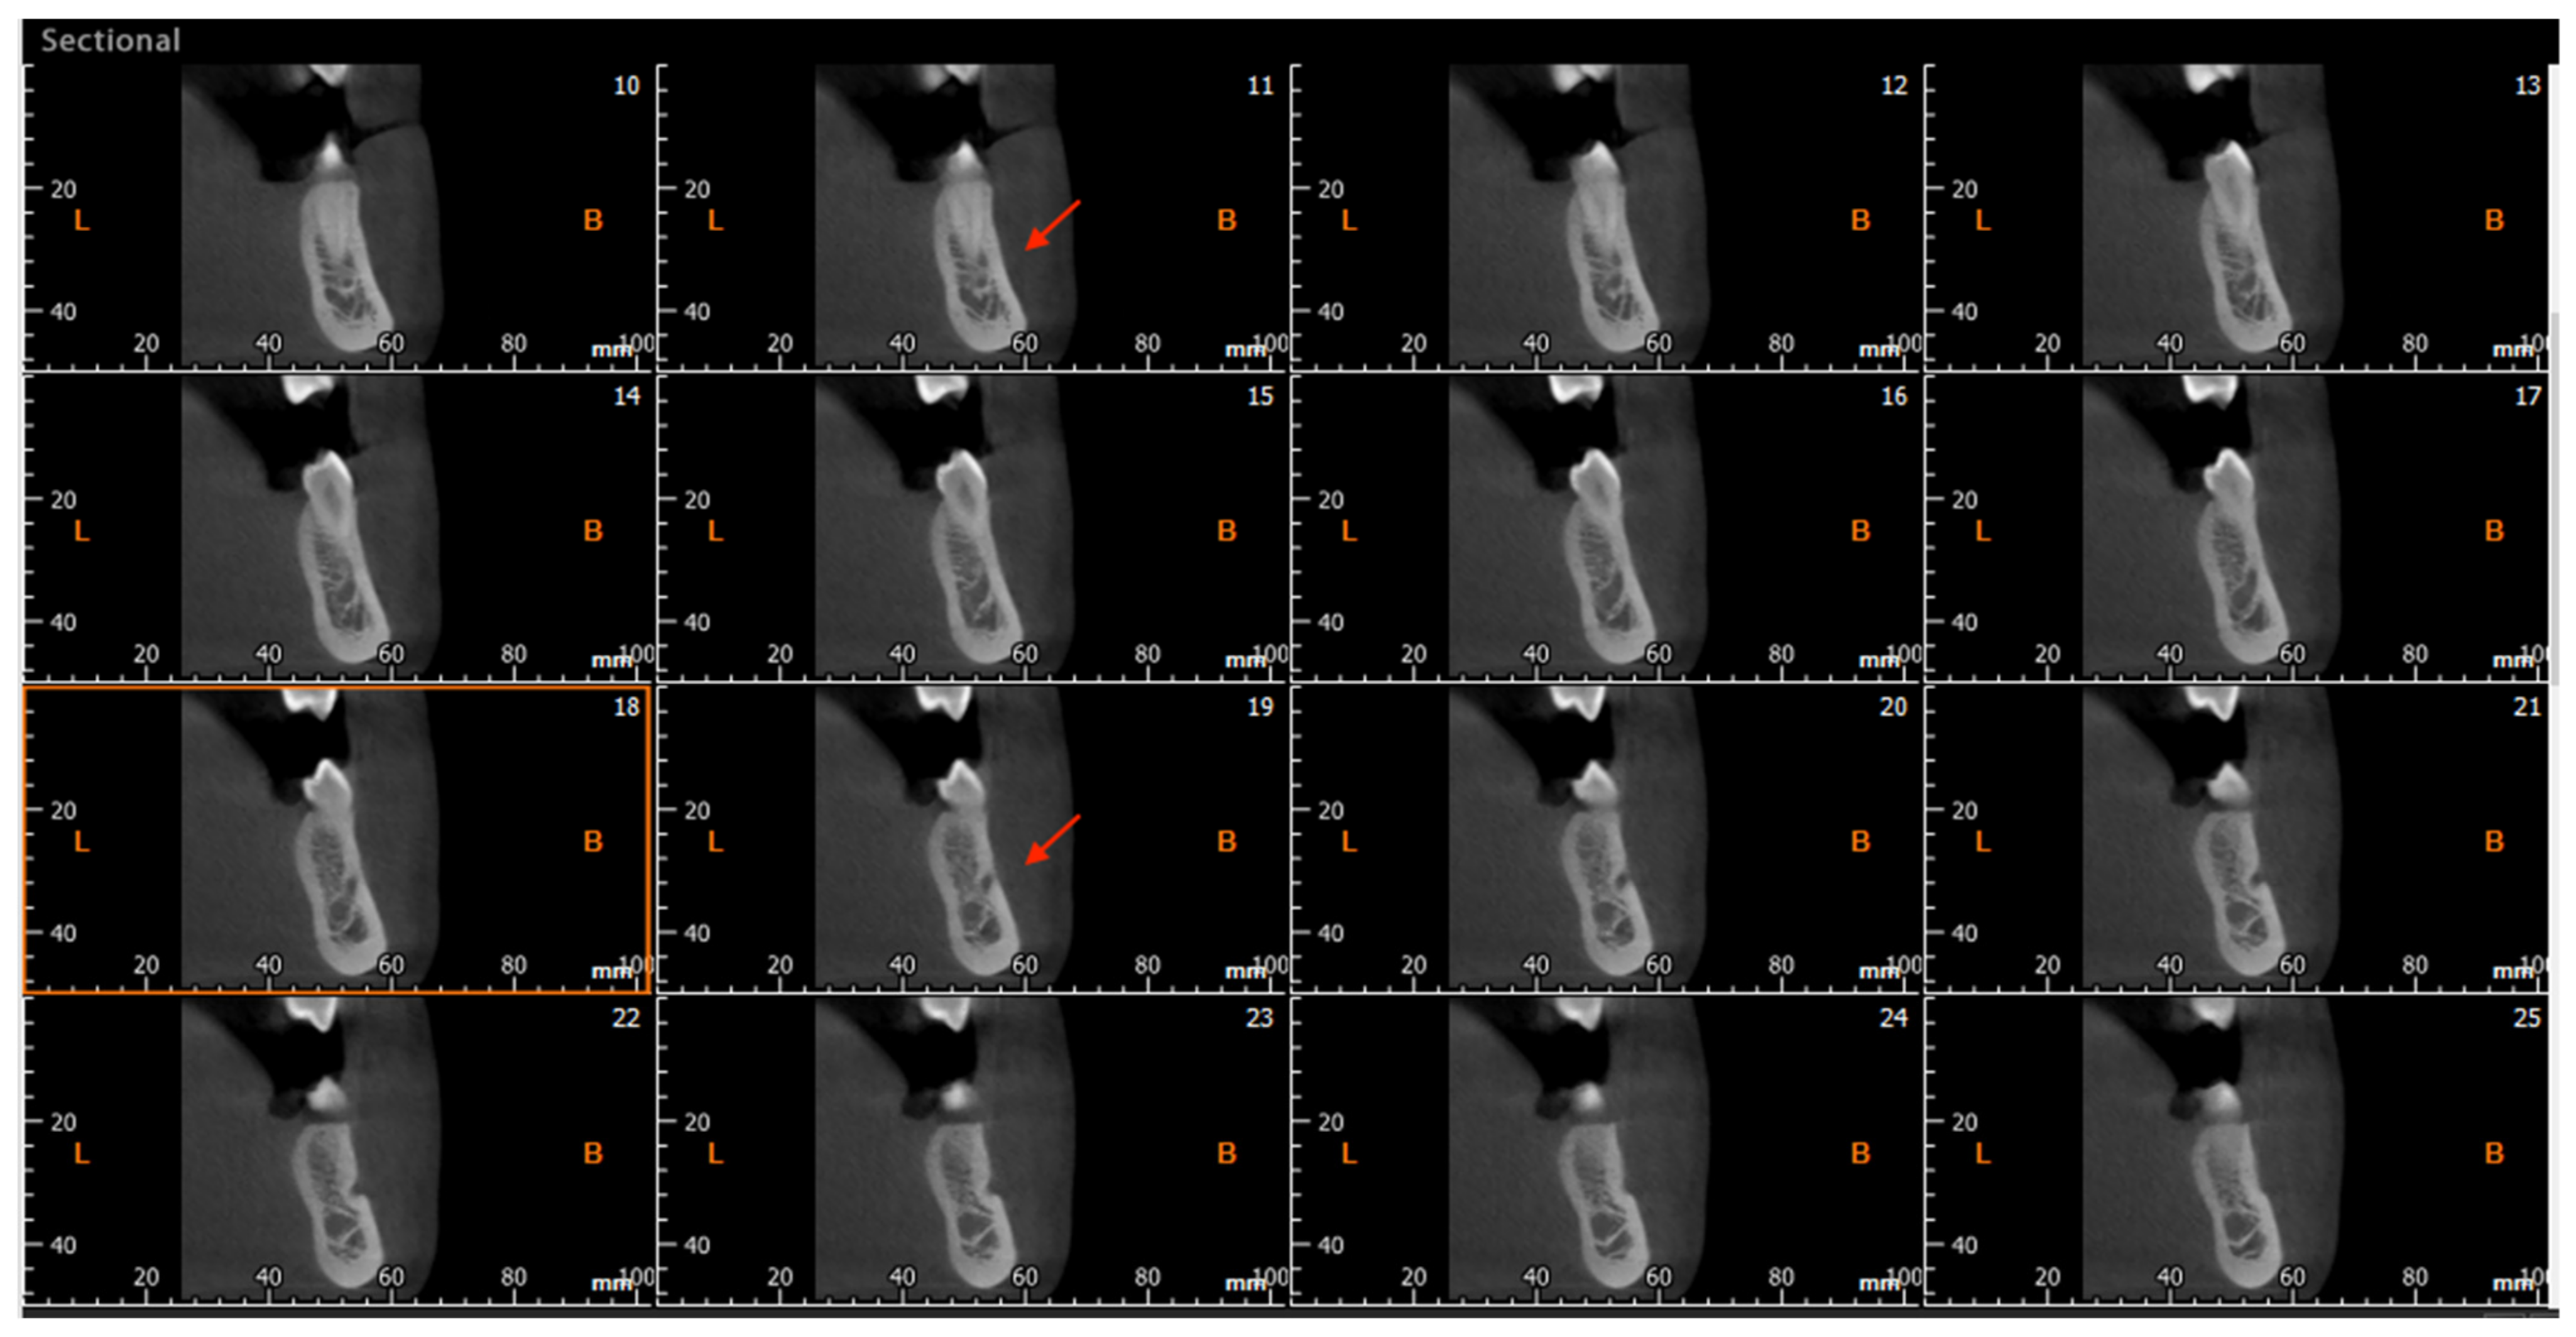

The CBCT study permits longitudinal and oblique rotation of the sections, as well as buccolingual and posteroanterior movements. It was possible to view and analyze the anatomical variants, such as the AL and the RC, using these movements. Once the structures had been identified, their presence was confirmed in every section (Figure 3). The length of the AL was determined by counting the sequential coronal sections from the anterior edge of the MF to the disappearance of the AL, multiplied by the thickness of the section (0.5 mm) (Figure 4).

Figure 4. Cross-sectional CBCT reconstruction. The anterior loop is visible in images No. 11–19 (red arrows). The length was measured as 9 × 0.5 = 4.5 mm. In image No.18 (highlighted with an orange square), the junction of the loop with the mandibular canal is observed, making the canal appear ‘wider’.